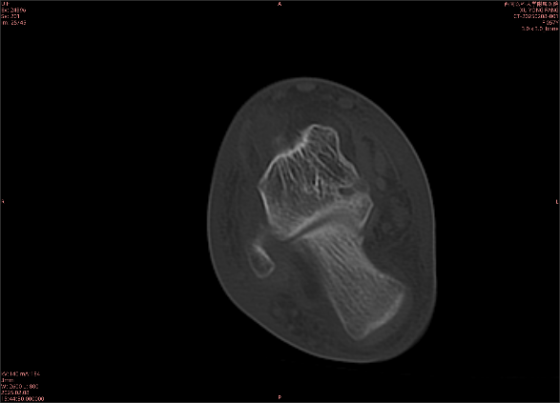

舉例圖像

圖2

專業(yè)解釋看不懂沒關(guān)系,大家看圖1和圖2就可以了,這是同一個(gè)患者跟骨的磁共振和CT圖像,圖1的紅色箭頭指示的黑線就是磁共振圖像顯示的骨折線,一目了然。而對(duì)比圖2的CT圖像上并未顯示異常。

這下大家明白了吧,如果懷疑隱匿性骨折優(yōu)先選擇磁共振檢查